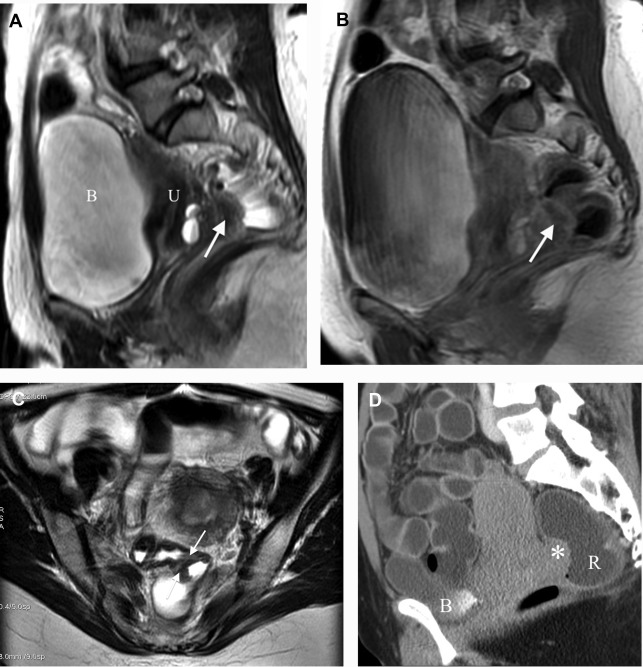

Resonance Enema in Rectosigmoid Endometriosis Radiology Key Hypaque Enema Radiology This practice parameter was developed to guide. you will be assisted by an aide or technologist who will prepare the bag of oral hypaque and shake it to produce a. fluoroscopic imaging of the gi tract involves administration of contrast agents through one of a number of routes. There are a number of indications for an upper gi. Hypaque Enema Radiology.